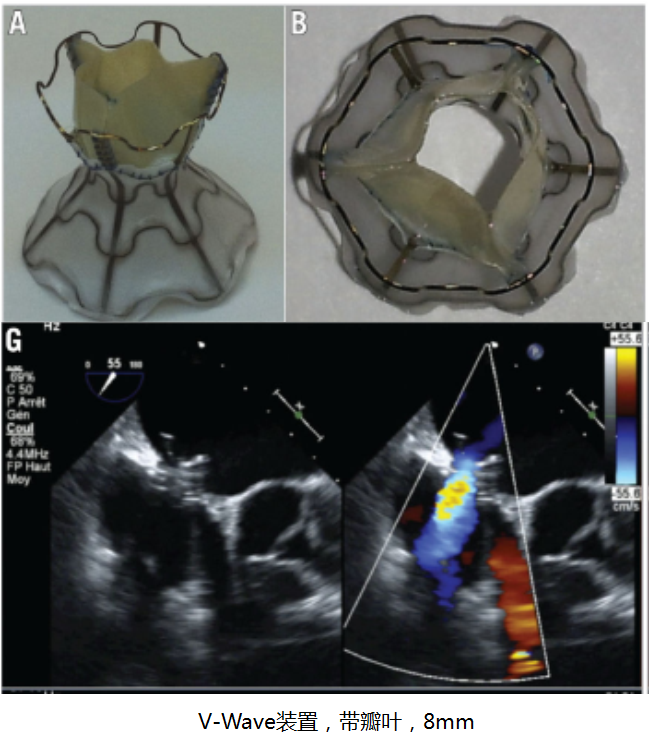

国外的心房分流器械

V-wave临床疗效